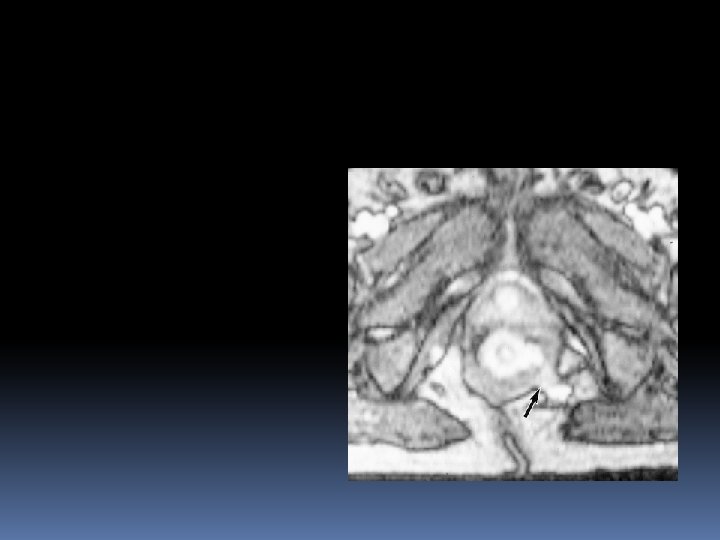

Extrasphincteric fistula A small abscess in left ischeoanal fossa , the fistula runs through levator ani , it is therefore above the sphincter complex and extrasphincteric